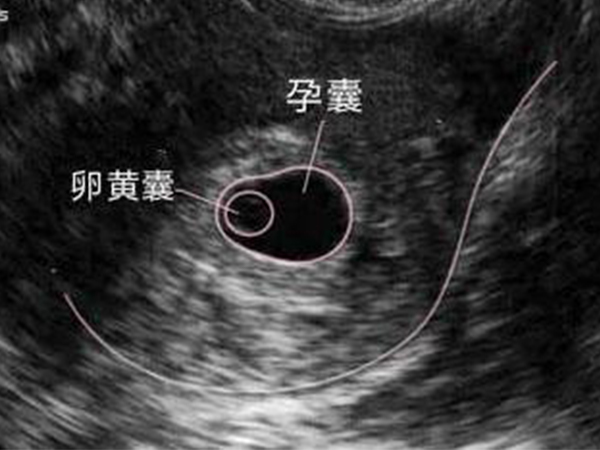

卵黄囊对于胎儿发育来说是非常重要的一个组织形式,一般出现在4~12周,是孕囊内部组织,是胚胎早期形成血管和组织的部位,然后在孕八周以后,胎盘会逐渐形成,也就会逐渐代替卵黄囊的功能,从而随着胎儿的发育,卵黄囊也会逐渐萎缩,到孕12周后卵黄囊就会慢慢消失。

很多女性在孕初期做B超检查都会听到卵黄囊一词,卵黄囊其实就是孕囊的内部组织,一般在35天后被发现,卵黄囊其实是一种胚胎组织,对胚胎发育来说至关重要,如果没有卵黄囊,那么这个孕囊就相当于是一个空壳,有很大的几率会发现停孕。

卵黄囊是孕囊的内部组织形式

卵黄囊对胎儿发育来说虽然非常重要,是作为判断孕囊是否正常的一个标准,但是卵黄囊一般是不会一直存在的,卵黄囊出现的时间在怀孕4~12周的时候,孕4周的时候卵黄囊会逐渐生成,直到孕5周被检查发现,然后到孕8周后逐渐被吸收,到孕12周后逐渐消失。